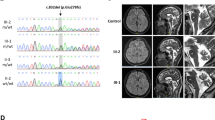

Here, we report four SCAR16 and nine SCA48 patients from two SCAR16 and five SCA48 unrelated French families. All presented with slowly progressive cerebellar ataxia. Additional findings included cognitive decline, dystonia, parkinsonism and swallowing difficulties. The age at onset was highly variable, ranging from 14 to 76 years. Brain MRI showed marked cerebellar atrophy in all patients. Phenotypic findings associated with STUB1 pathogenic variations cover a broad spectrum, ranging from isolated slowly progressive ataxia to severe encephalopathy, and include extrapyramidal features. We described five new pathogenic variations, two previously reported pathogenic variations, and two rare variants of unknown significance in association with STUB1-related disorders. We also report the first pathogenic variation associated with both dominant and recessive forms of inheritance (SCAR16 and SCA48).

Even though differences are observed between the recessive and dominant forms, it appears that a continuum exists between these two entities. While adding new symptoms associated with STUB1 pathogenic variations, we insist on the difficulty of genetic counselling in STUB1-related pathologies. Finally, we underscore the usefulness of DAT-scan as an additional clue for diagnosis.